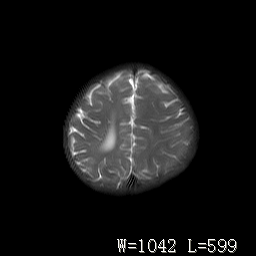

标题: PED3252:脑室增大。

女,3岁,3岁不会说话,阵发性抽搐、自伤。

右侧额叶发育不良!

右侧额叶发育不良。

右侧额叶发育不良